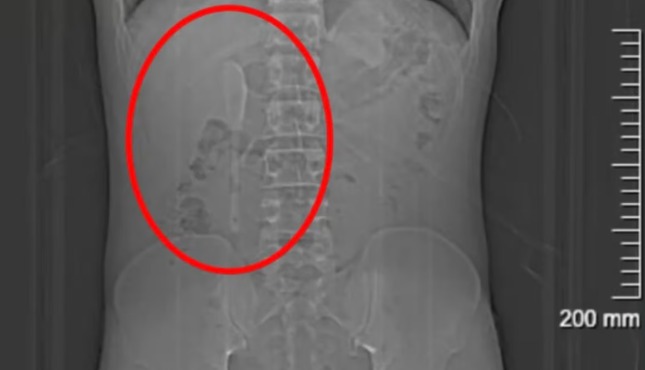

No hospital, exames de imagem revelaram o insólito diagnóstico: uma colher de aproximadamente 15 centímetros estava alojada em seu duodeno, parte inicial do intestino delgado. Segundo os médicos, a remoção era complexa devido à superfície escorregadia do objeto e à sua posição, que oferecia risco de perfuração intestinal, inflamações ou sangramentos.